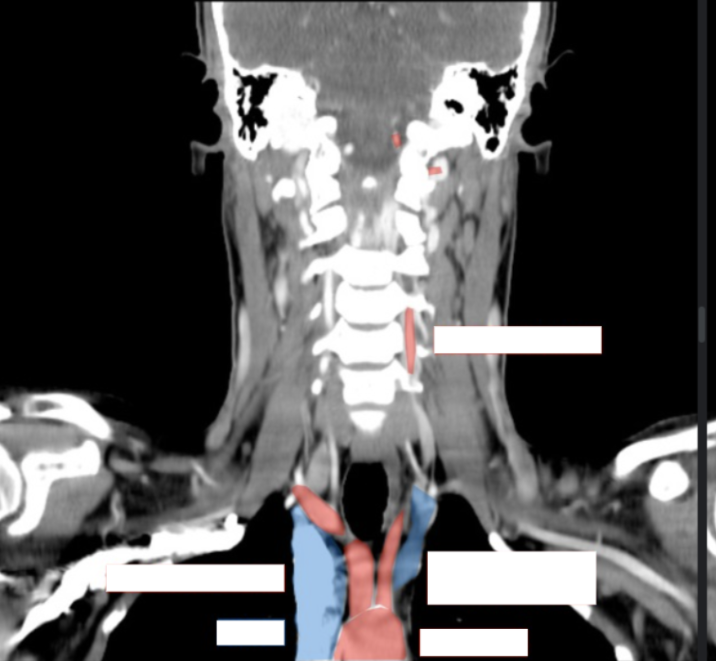

Please label this coronal CT scan